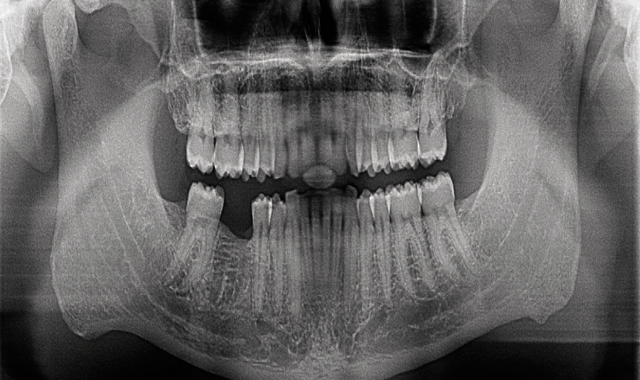

Fig. 3 Virtual planning implant tooth # 30, using CS 3D imaging software

Next, I take a 3D scan using my in-office cone beam computed tomography (CBCT) system (Carestream Dental’s CS 9300C) (Fig. 3). For as long as I can remember, having 3D information has been an important part of my implant planning and placement-I would even send my patients out for scans before I incorporated a unit into my practice. I consider 3D imaging to be the standard of care when it comes to implant procedures as it allows me to more accurately identify the morphology of the bone than 2D imaging alone.2

Using Carestream Dental’s CS 3D Imaging software, I can virtually assess the area to determine if there is enough bone to continue or if a sinus lift, bone graft or other procedure is necessary first. If the patient is ready for an implant at that time, I can also assess the complexity of the case to determine if a surgical guide is necessary.